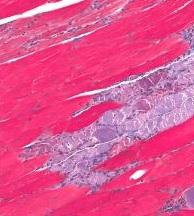

La myostatine est une protéine naturellement produite dans le corps qui inhibe la croissance musculaire, rappelle le Dr Stuart Warden, professeur agrégé et auteur principal de l'étude. Le rôle de la myostatine est en effet de contrôler la réparation et la croissance musculaire en bloquant la prolifération des cellules musculaires. Plusieurs études y ont donc déjà vu une cible prometteuse pour le traitement de certaines myodystrophies (Voir visuel "muscle avec dystrophie" ci-contre). En effet, inhiber l'activité de cette molécule peut permettre de prolonger la prolifération des cellules musculaires, augmenter la masse et la puissance musculaires. Certains sportifs y ont également vu des bénéfices musculaires… Finalement, cette étude apporte à la preuve que l'inhibition de la myostatine peut permettre aux muscles de se développer ou a minima de ne pas décliner.